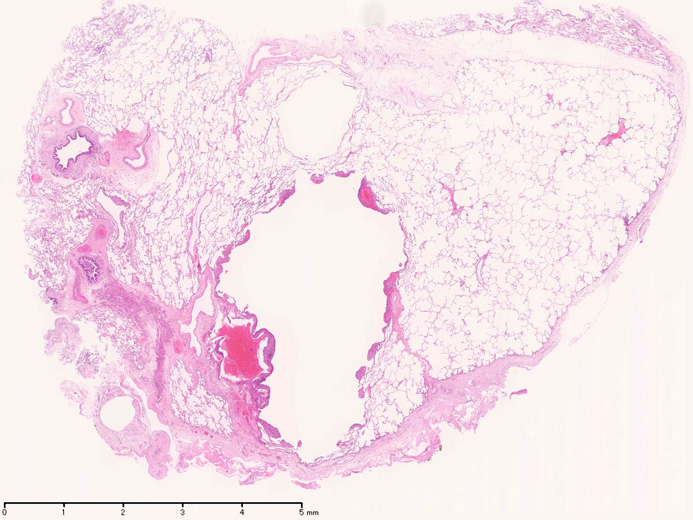

LAMの組織病理

LAMの肺病変

嚢胞周囲または肺血管, リンパ管, 細気管支にそうLAM cellの浸潤, 集簇を特徴とする。LAM cellには2種類が認められ, 小型紡錘形細胞と細胞質の豊富な類上皮様細胞があり, 紡錘型は主に集簇巣の中心に存在し増殖能が高い。 類上皮様LAM cellは辺縁部に多く, 増殖能は低いがHMB45を強く発現している。

LAM cellの免疫染色--SMA, desmin, vimentin(vimentinはいつも陽性とはならない)が陽性となりmuscle lineageであるが典型的な筋細胞と異なり,

嚢胞形成はLAM cellの増殖と関連しており, 細胞が産生するmatrix metalloproteinases(MMPs)による組織破壊によるらしい。